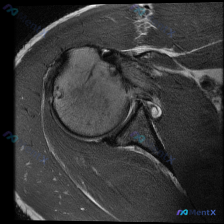

看到一份肩关节MRI的病例材料,是T1加权序列的冠状位图像。用户想了解盂唇病变的可能性,先整理一下目前能看到的信息: 基础观察: - 解剖结构清晰,肱骨头、关节盂、肩胛骨、肩峰都显示良好 - 冈上肌肌腱从肌腹到肱骨大结节止点连续 - 关节盂唇形态尚可,但T1序列对细微病变的敏感度有限 - 肱骨头后上...

看到一个肩部MRI病例(T1序列、冠状位),原问题是关于盂唇病变的,但我在看的时候发现冈上肌腱的信号异常好像更明显。大家先看影像,你会怎么考虑?

最近看到一个髋关节MRI病例,提供的是单帧T1冠状位影像,临床怀疑盂唇病变。但T1序列对软组织的分辨率有限,尤其是对盂唇这样的结构。大家基于这张影像,对盂唇病变的诊断有什么思路?或者有哪些其他的考虑方向?欢迎讨论!